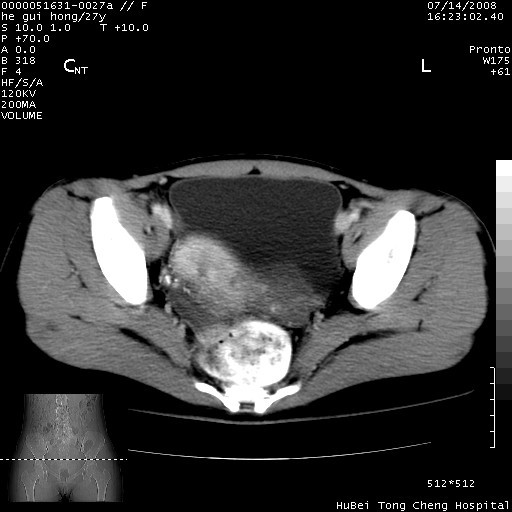

以下是引用杀毒软件在2008-7-20 8:03:00的发言:[br]支持双侧卵巢囊腺瘤可能性大!

以下是引用zjzjr在2008-7-20 13:36:00的发言:[br]双侧附件囊腺瘤可能性大!